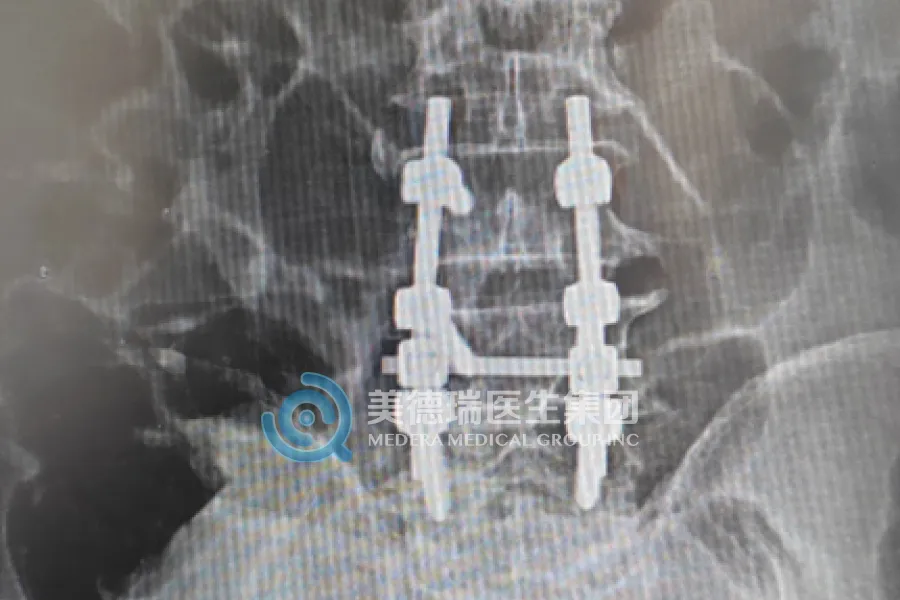

近期,该中心已常态化开展包括膝关节置换、人工股骨头置换、关节镜下半月板缝合、腰椎融合及椎板减压术等在内的多项核心术式,覆盖了关节、脊柱、运动医学等多个领域,标志着中心已从单纯的“技术引入”迈向了“能力扎根”的全新阶段,区域骨科诊疗水平实现了实质性的飞跃。

对于腰椎疾病患者,腰椎融合及椎板减压术则能精准解除神经压迫,重建脊柱的稳定性,提供可持续的改善方案。